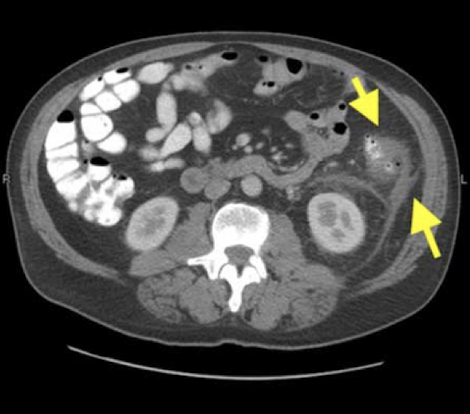

Acute appendicitis

CT Abdomen/Pelvis IV contrast

Diverticulitis

CT Abdomen/Pelvis IV contrast

Intra-abdominal abscess

CT Abdomen/Pelvis IV contrast